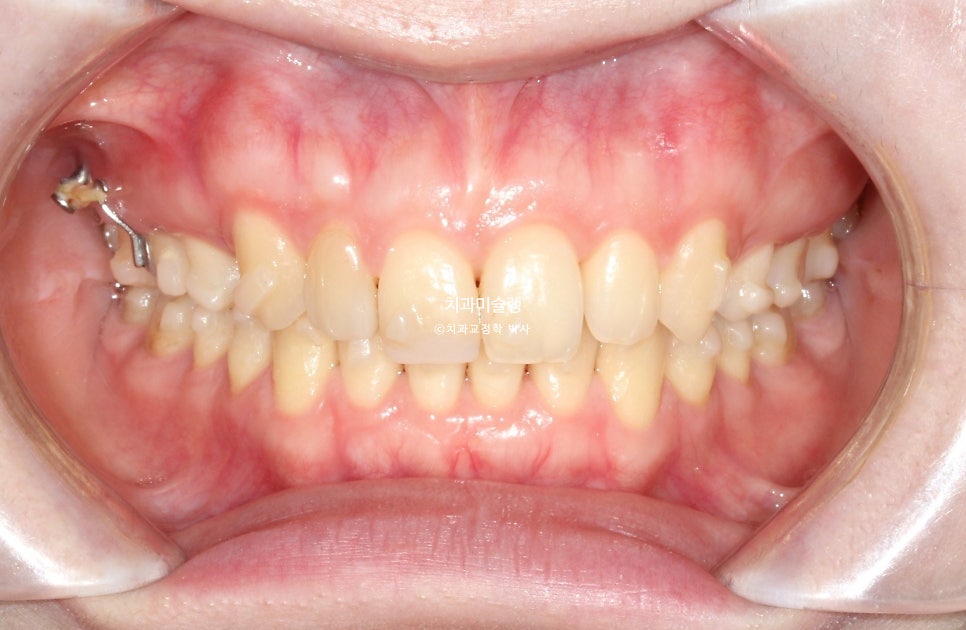

23년 4월, 교정치료를 위해 오신 20대후반 환자입니다. 실제론 앞니가 전반적으로 작은편임에도 불구하고 사진에서 앞니가 유독 커보이는건 돌출되어있기 때문입니다.

치열은 정면에서 볼때 원근법을 따르기에 튀어나와있으면 커보이고 뒤로갈수록 작아보이죠.

앞니 2개가 유난히 돌출되어 있습니다.

앞니뿐 아니라 어금니 교합관계가 2급입니다.

초진사진에서는 가운데 앞니가 커보였으나 교정후 사진에서 가운데앞니가 작아진것처럼 보이죠.

하지만 앞니 사이즈가 작아진게 아니라, 튀어나와있던 앞니가 뒤로 들어가며 비로소 본래 사이즈로 보이는것이랍니다.